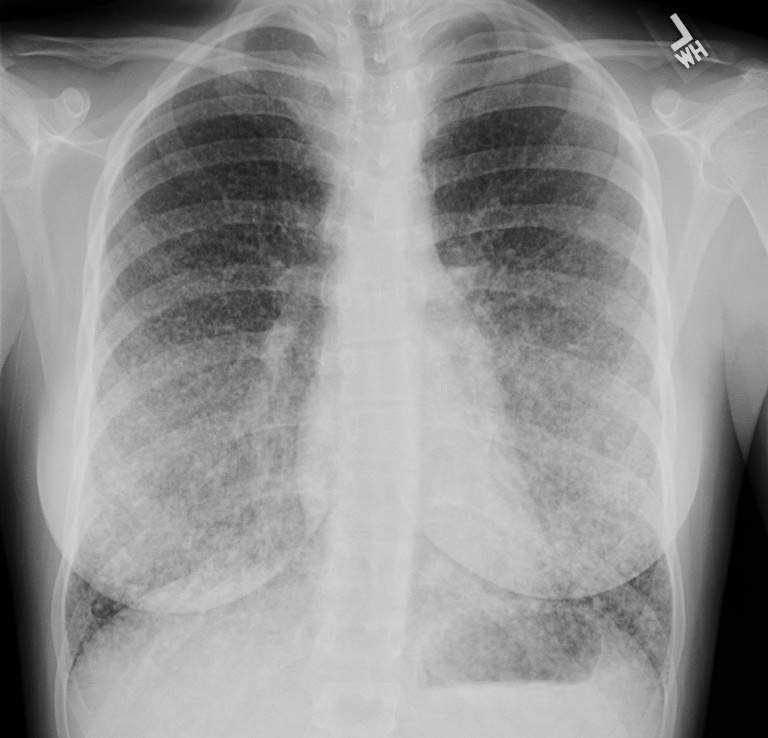

Metastatic thyroid cancer (miliary pattern); Diffuse micronodules